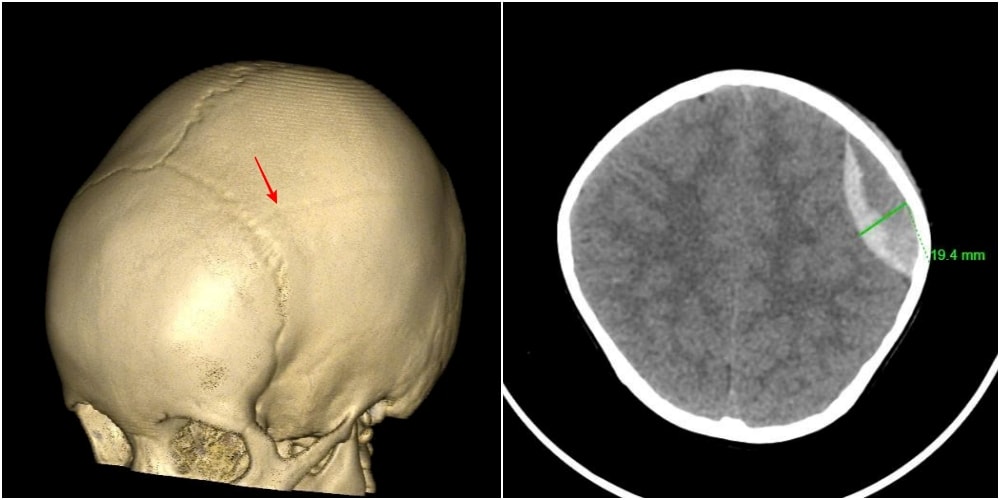

Kết quả chụp cắt lớp vi tính cho thấy, hình ảnh vỡ xương sọ, chảy máu ngoài màng cứng đỉnh trái. Các bác sĩ chẩn đoán bệnh nhi bị chấn thương sọ não do ngã, vỡ xương, tụ máu ngoài màng cứng đỉnh trái.

Ngay lập tức, các bác sĩ chuyên ngành Ngoại thần kinh phối hợp cùng khoa Gây mê hồi sức tiến hành phẫu thuật cấp cứu lấy máu tụ, cầm máu kỹ, đặt và cố định lại xương sọ. Ca mổ diễn ra thuận lợi trong khoảng 30 phút.